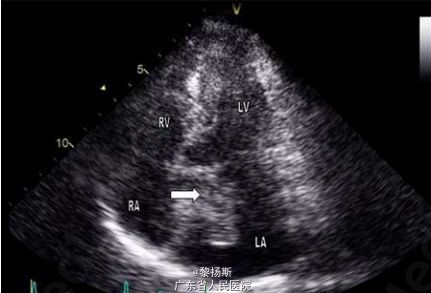

体格检查发现患者双侧膝盖网状青斑(图 1)。收入院时,患者体温 38.5℃,心率 165 次 / 分,呼吸 28 次 / 分,血压 89/50mmHg,血氧饱和度 94%(无额外吸氧)。心脏查体闻及 2/6 级全收缩期杂音,以心尖部最为明显,余检查未见明显异常。实验室检查发现白细胞增加至 15.7×109/L(参考值范围 3.8–11×109/L),中性粒细胞占 95%,血红蛋白 127g/L,血小板 306×109/L,C 反应蛋白升高至 73mg/L(参考值范围 0-5mg/L),另外,尿素和肌酐轻度增加,自身免疫抗体阴性,尿常规正常。心电图提示窦性心动过速,无 PR 间期延长,胸部 X 线检查无异常。血培养结果提示存在少酸链球菌(S. acidominimus),对青霉素和红霉素灵敏。进一步经食道超声心动图(TTE)检查提示左房纵向扩张,伴一大小为 2.8×3.2cm,附着于房间隔的部分活动性结构(图 2)。另外,二尖瓣上也附着有赘生物(图 3)。